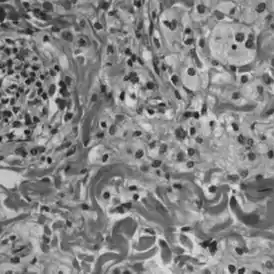

Для постановки диагноза ЭЧБ требуется проведение гистологических исследований. К типичным гистологическим признакам ЭЧБ относятся локализованные вдоль участков фиброза полиморфные ксантогранулемы, состоящие из CD68+, CD1a-, S100- пенистых гистиоцитов. При лангергансоклеточном гистиоцитозе, представлены гистиоциты классов CD68+, CD1a+.